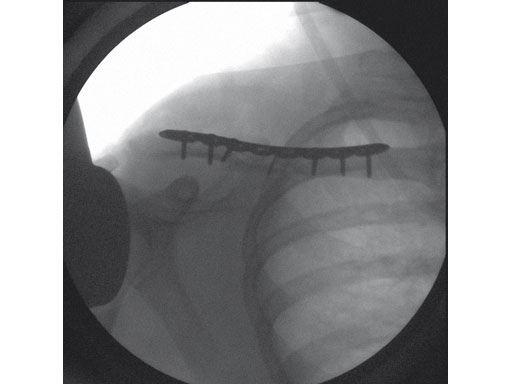

Fig 3 3.5 mm LCP superior clavicle.

Fig 1ab Preoperative x-rays.